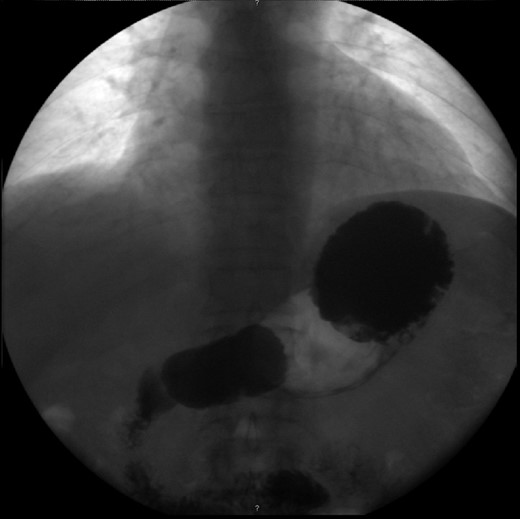

An upper endoscopy was performed, revealing a severe esophagitis with a distortion of the gastric anatomy. A great amount of stasis fluid and multiple ulcerations of the gastric fundus were present. An upper gastrointestinal series was also performed, revealing an inverted stomach, with the atrum being positioned superiorly to the fundus, with an abnormal position of the pylorus (Fig. 2).

Upper gastrointestinal series, revealing an inverted stomach, with the atrum being positioned superiorly to the fundus and a stretched duodenal arch, with an abnormal position of the pylorus.